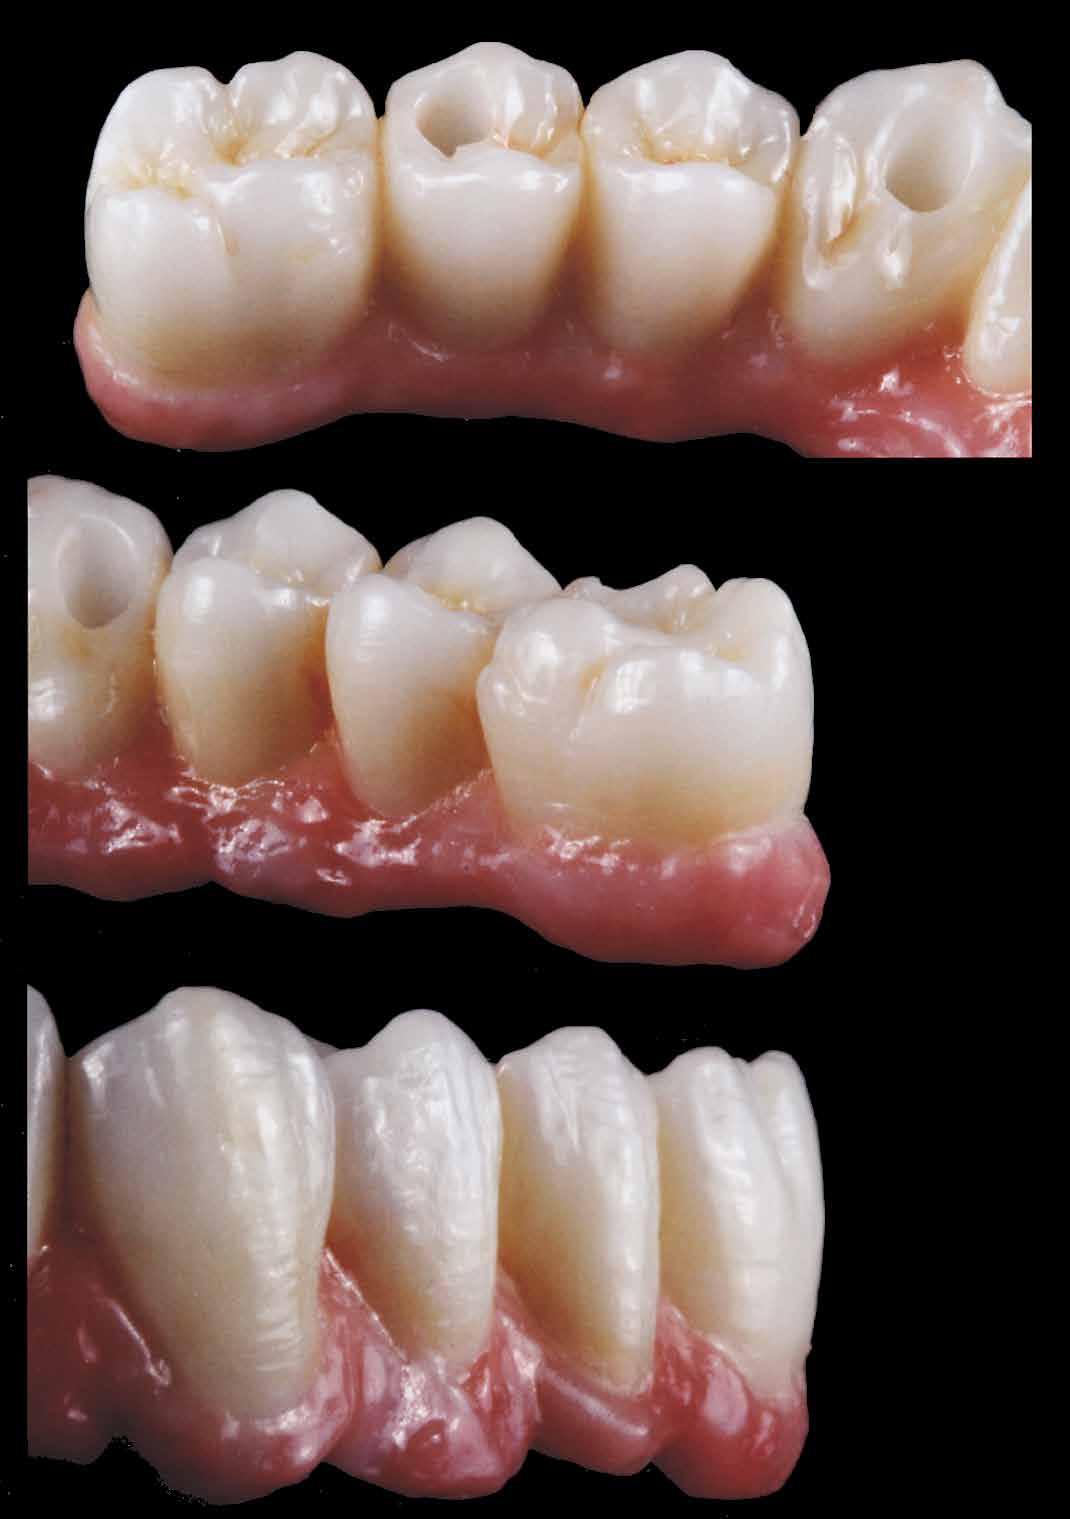

ÚJ PARADIGMA AZ ESZTÉTIKAI HELYREÁLLÍTÁSBAN

Fontfogak esztétikai helyreállítása KATANA™ UTML teljesen anatómikus koronákkal, vesztibuláris leplezéssel és Biológiailag

Orientált Preparálási Technikával (BOPT)

Dr. Marco Nicastro (Olaszország) A kiindulási állapot és a végeredmény. A KATANA™ UTML kiváló esztétikai tulajdonságokkal rendelkezik, és tökéletesen, harmonikusan illeszkedik a rózsaszín szövetekkel.

1. ábra: A beteg esztétikai problémájára kért megoldást a régi restaurációk természetellenes megjelenése, továbbá a múltban lezajlott periodontitis következtében kialakult fekete háromszögek miatt. A szövetek visszahúzódása következtében a fogpótlás széle jól láthatóvá vált, a papilla csúcsok elvesztése és a koronák közötti számos fekete térrel együtt, komplex terápiás ellátást igényelt.

2. ábra: A parodontális problémák nem sebészeti kezelési terve a következőkből állt: fogkő-eltávolítás és gyökérsimítás, a korábbi rögzített fogpótlás cseréje, a marginális szövetek helyreállítása, és egy új, esztétikailag kedvezőbb gingivális szerkezet helyreállításának megkönnyítése.

16. ábra: Klinikai fotó egy évvel a PANAVIA V5-tel történő beragasztás után. A marginális szövetek jó klinikai állapotát látjuk, semmi jele gyulladásnak vagy vérzésnek. A BOPT lehetővé teszi számunkra, hogy optimalizáljuk a gingiva szintjét anélkül, hogy parodontológiai sebészeti beavatkozáshoz folyamodnánk, miközben az új koronák alakja lehetővé tette az interproximális terek zárását az optimális esztétikai eredmény érdekében.

17. ábra: A fogpótlás világossága (főleg a transzlucentes cirkónium használatának köszönhetően), a metszők alakjával kombinálva nagymértékben javította a pótlás esztétikáját, még akkor is, ha a kiindulási helyzet különösen kedvezőtlennek tűnt.

18. ábra: Az előző fogpótlással összehasonlítva a metszők redukálása nem csak azt tette számunkra lehetővé, hogy optimalizáljuk a funkcionális fázist az overjet csökkentésével, hanem lehetővé tette a még esztétikusabb eredmény elérését azzal, hogy a metszők élének kontúrjával követni tudtuk az alsó ajkat.